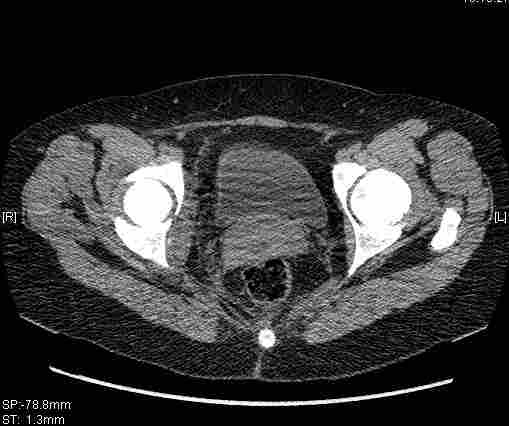

Удалось сегодня вывести пациентку в соседнюю больницу, где есть кт. Срезы сделаны только горизонтальные.

Следом 3d

Приветствую,Антон.Рункова рядом нет,но после полученных данных КТ,обсуждали совместно.Итог обсуждения-развернутый ответ дать не получится,т.к.срезы выбраны не информативные.Если ориентироваться на данные 3D,то ,ИМХО,можно лечить на вытяжении.